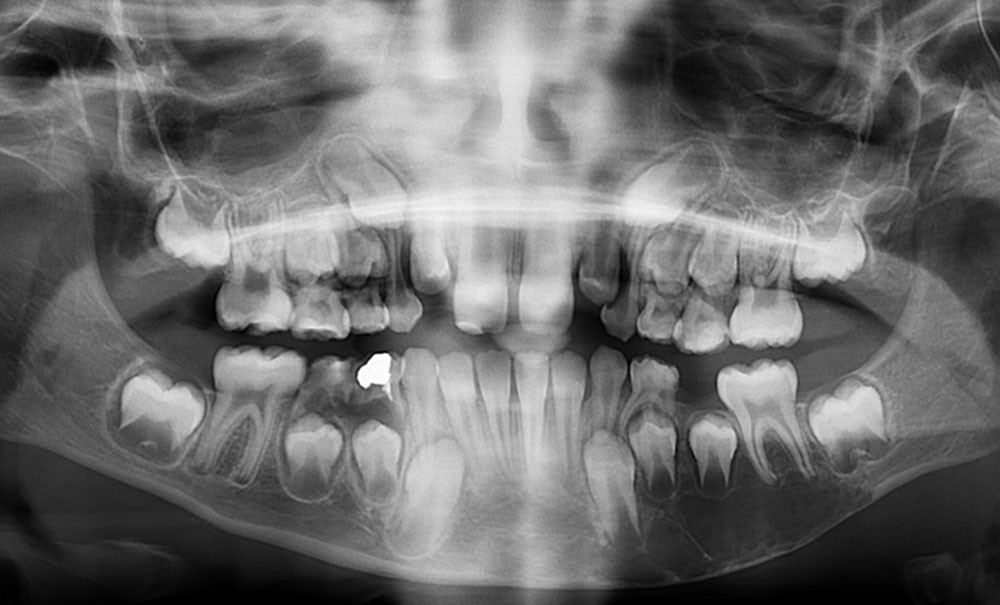

Il existe une zone ostéolytique unique, aux contours extrêmement fins, évidant la branche horizontale de la mandibule, et dont la limite supérieure est mieux marquée et dite « circinée », contournant les racines dentaires.

Le diagnostic est fait lors de l’intervention : la cavité est « vide », ne contenant aucune poche kystique (fig. 5).